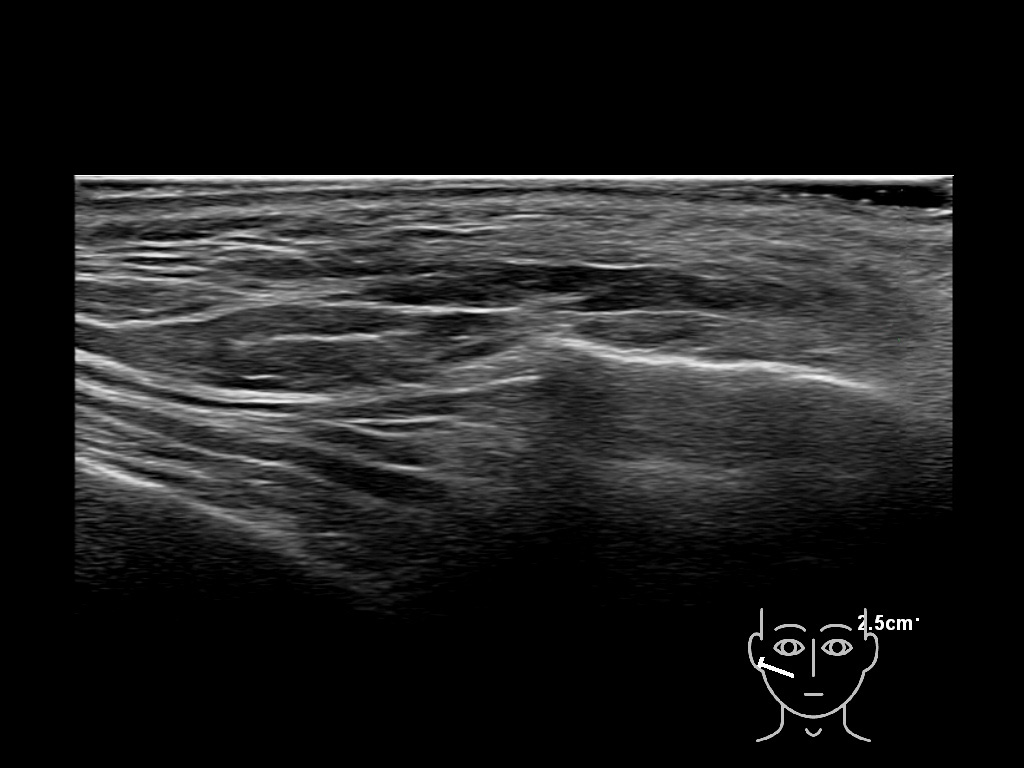

Filler behavior - Temple zygoma US

Study the first image to recognize the different layers. If you are sure about the layers, swipe to the second image to view the answer (if applicable).